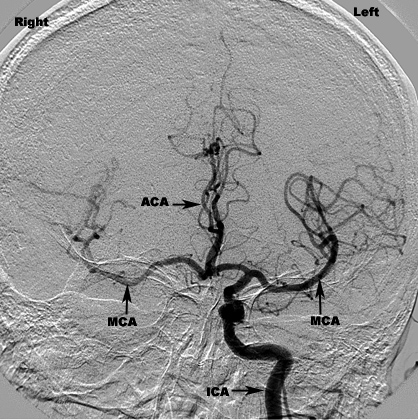

Brachial Angiography For The Evaluation Of Carotid Artery ...

Brachial Angiography for the Evaluation of Carotid Artery Occlusion in the Treatment of "Posterior Communicating"Aneurysm1 IRVIN 1. KRICHEFF, M.D., NORMAN E. CHASE, M.D., JOSEPH PEN·TZE LIN, M.D., and ... Get Document